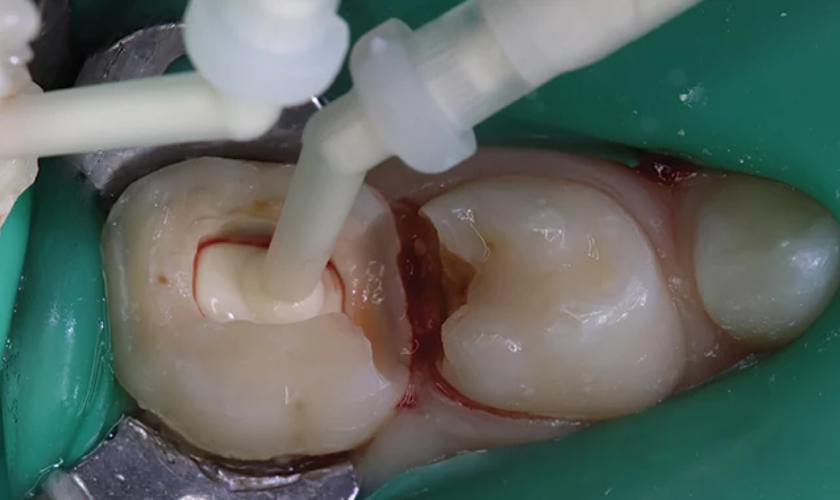

- Accessing the Pulp: The dentist will create a small opening in the tooth to access the pulp chamber.

- Pulp Removal: The infected portion of the pulp is carefully removed.

- Medication: A medicated material is placed to promote healing and prevent further infection.

- Sealing the Tooth: The tooth is sealed with a filling material to prevent bacteria from re-entering.